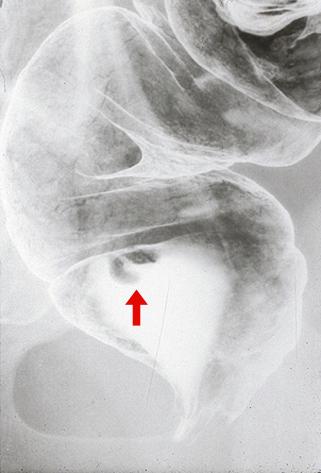

Carcinoide del Recto de 1 cm. de diámetro mayor acompañado de ulceración central y evidencia de metástasis a ganglios linfáticos

[Image-ID:3864]

Tumor Carcinoide/

colon/recto

Rayos X

diámetro mayor del tumor

10 - 14

grado de penetración

sm